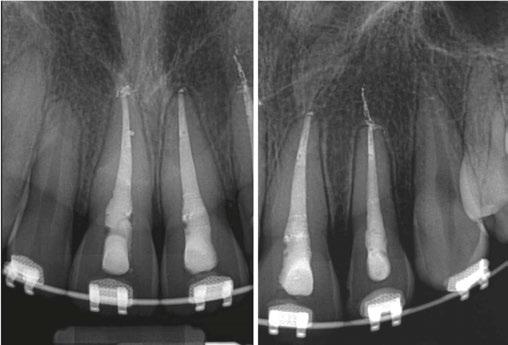

Two days after treatment, the patient was seen in my practice after the teeth were splinted back in place by the orthodontist. Figures 2A-2B are the preoperative radiographs after the teeth were reimplanted.

One can already appreciate the inflammatory resorption that is occurring at the apices of teeth Nos. 9 and 10. These images were taken just two days after the trauma.

Figures 2A-2B